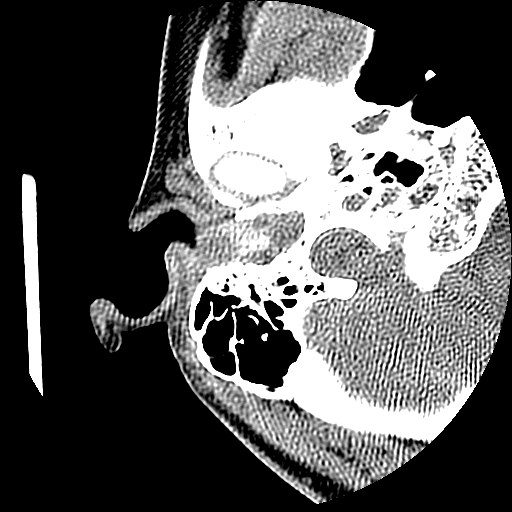

以下是引用随光逐影在2009-8-19 7:25:00的发言:[br]右侧慢性中耳乳突炎,右侧中耳腔及外耳道肉芽肿或胆脂瘤形成。